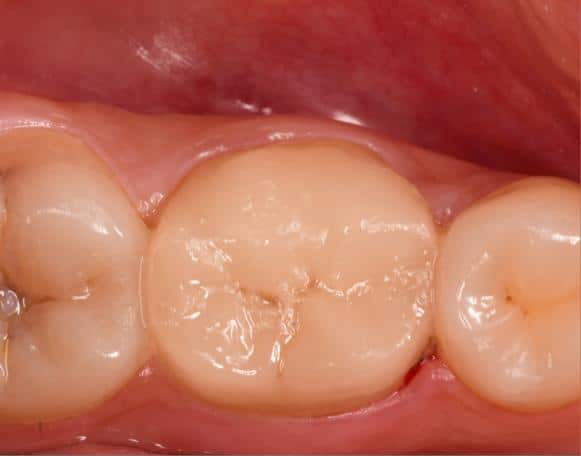

Immediate result

Contact

Occlusal view